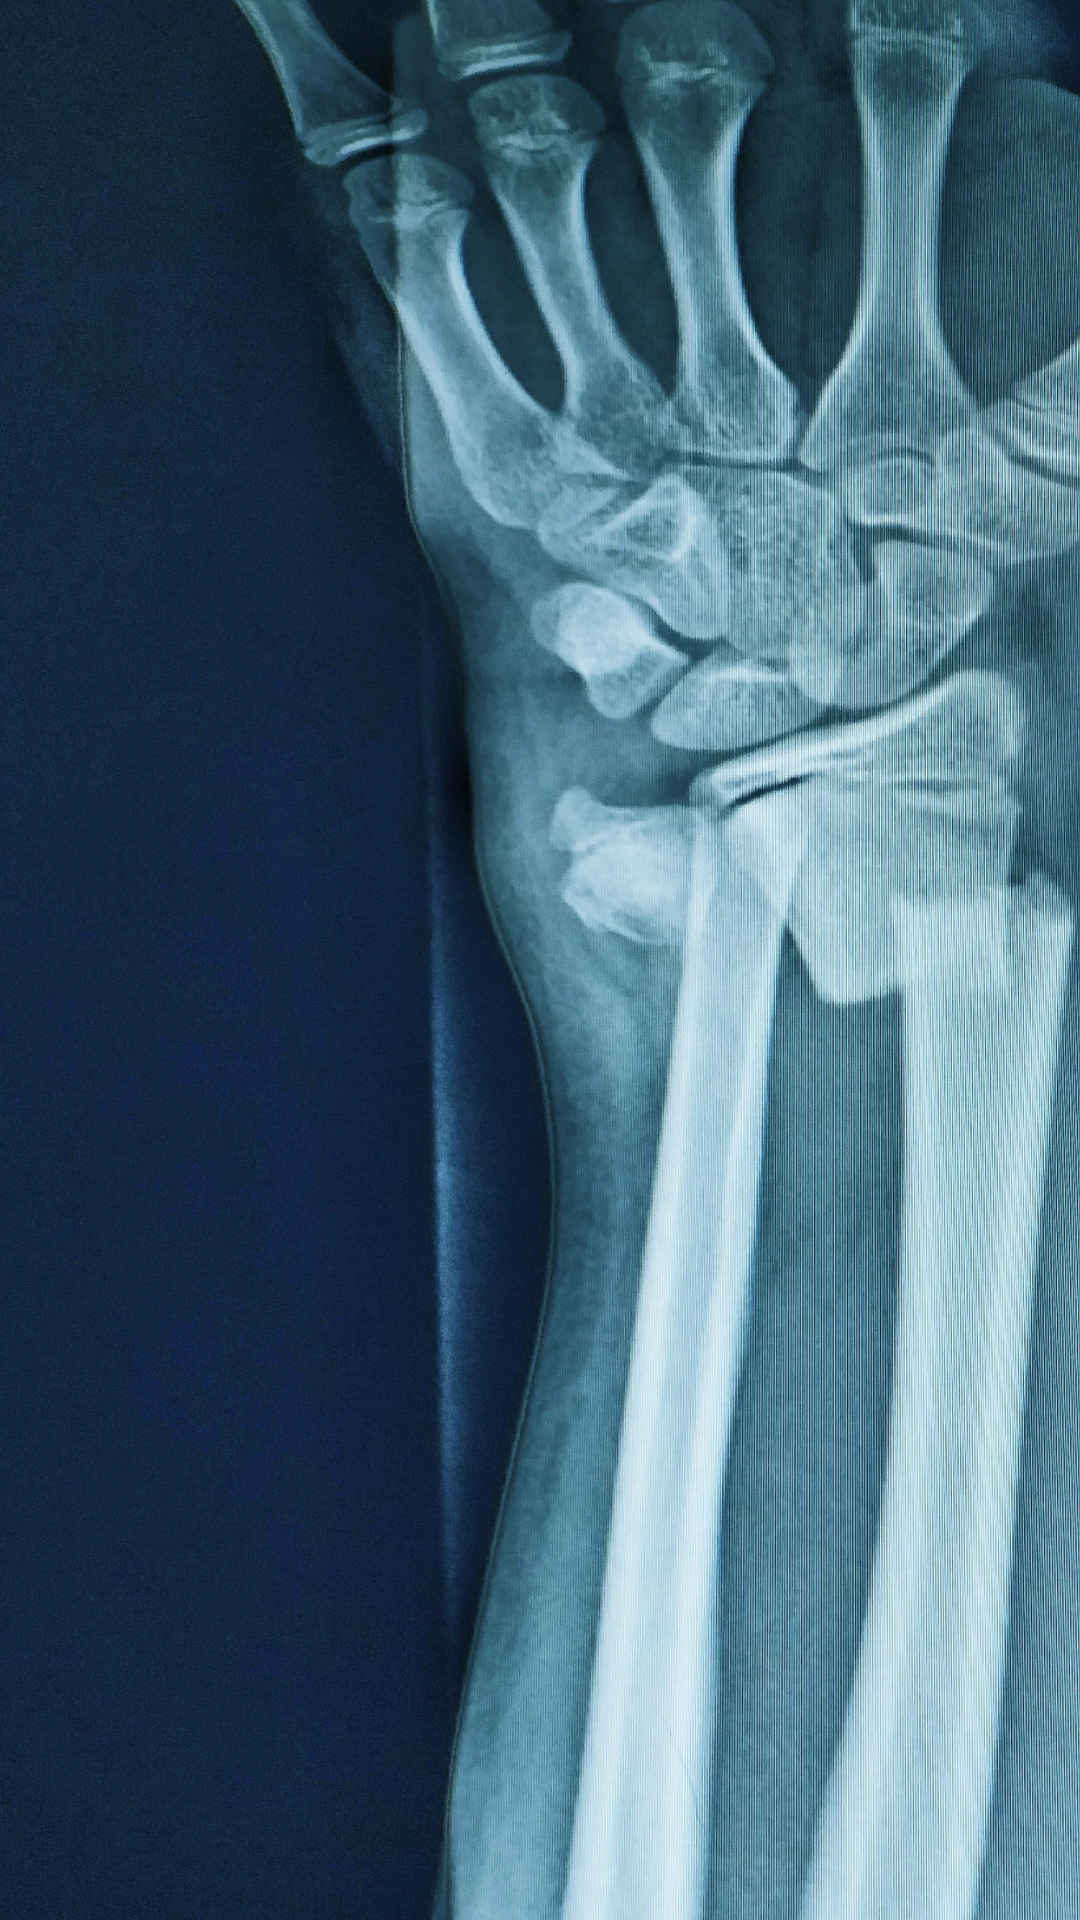

Los tratamientos quirúrgicos de las fracturas van desde la reducción cerrada o abierta de la fractura (alineación de los fragmentos) y fijación con implantes. La fijación puede ser interna o externa.

Para una recuperación exitosa, el diagnóstico es básico. En CIFO nuestros pacientes son valorados minuciosamente, utilizando herramientas clínicas y haciendo uso de la tecnología diagnóstica más avanzada.